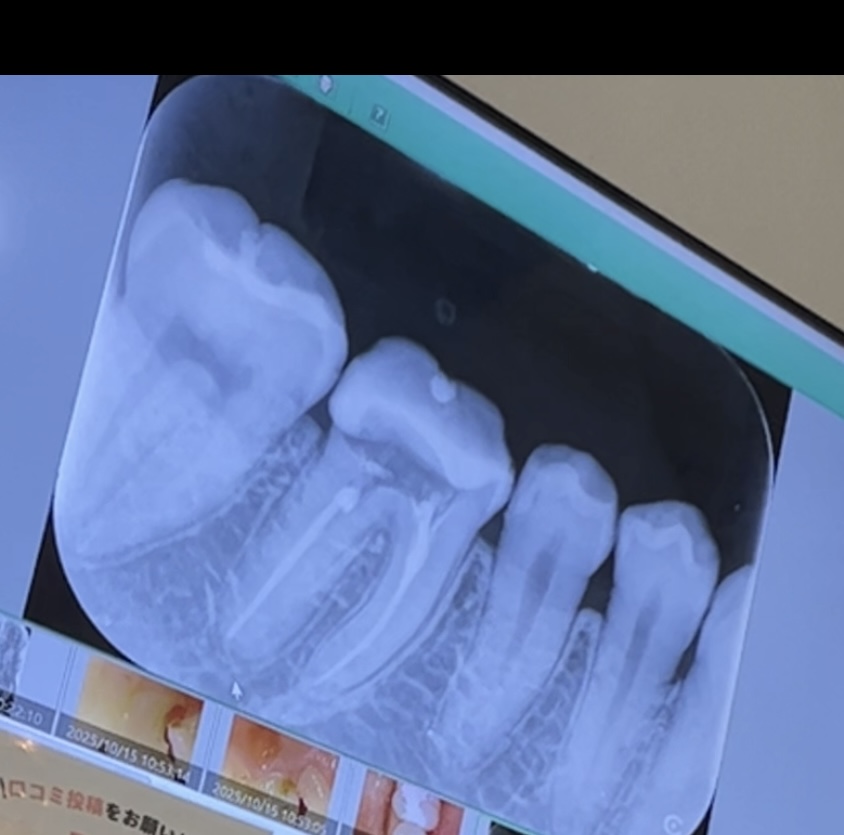

根管治療後の歯に冷たいものがしみたり、ズキズキします。回答数:2

根の治療後から歯が痛むようになりました。回答数:2

歯の神経を抜きましたが、まだ痛みがありしみます。よくあることですか?回答数:2

自費で再根管治療をした歯の痛みが続いています。回答数:2